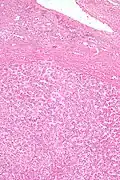

Los adenomas hepáticos son, típicamente, nódulos bien circumscriptos que constan de hojas hepatocitarias con un citoplasma vacuolado de aspecto burbujeante. Los hepatocitos se disponen en un armazón de reticulina regular y más o menos igual a tres células de espesor.

El diagnóstico histológico de los adenomas hepáticos puede ser facilitado por la impregnación argéntica (tinción con sales de plata). En los adenomas hepáticos, el armazón de reticulina y los hepatocitos no forman capas de cuatro o más hepatocitos, como se ve en el carcinoma hepatocelular.

Las células parecen hepatocitos normales y son recorridos por vasos sanguíneos pero carecen de espacios porta y venas centrales.

Micrografía de adenoma hepático. Tinción hematoxilina-eosina. -